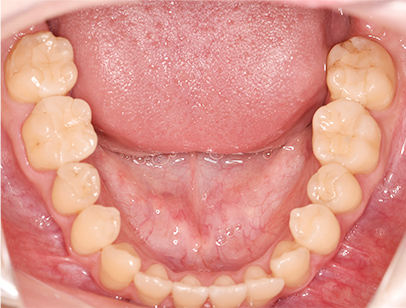

症例02|20代の男子

前歯部の反対咬合の症例

上下の前歯が反対咬合を主訴として来院されました。通常通り検査を行い「反対咬合」と診断されました。

治療計画

下の犬歯から後ろの歯をまずは後方に移動して、その後に上下の歯並びを綺麗に並べて前歯部の咬み合わせを改善することにしました。

矯正の種類

カリエールディスタライザー、上に裏側、下に表側のセラミック(白い矯正装置)

治療前の写真を治療後の写真を比べると、鼻の下がくぼんでいたのが改善されて口元が綺麗になった事が解ります。また歯並びは綺麗に並び上の歯が前に出て下の歯が後ろに移動して歯がしっかりと咬み合っています。

患者様に協力いただけたため、2年の治療期間で終了することができました。